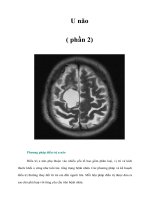

U não

( phần 1)